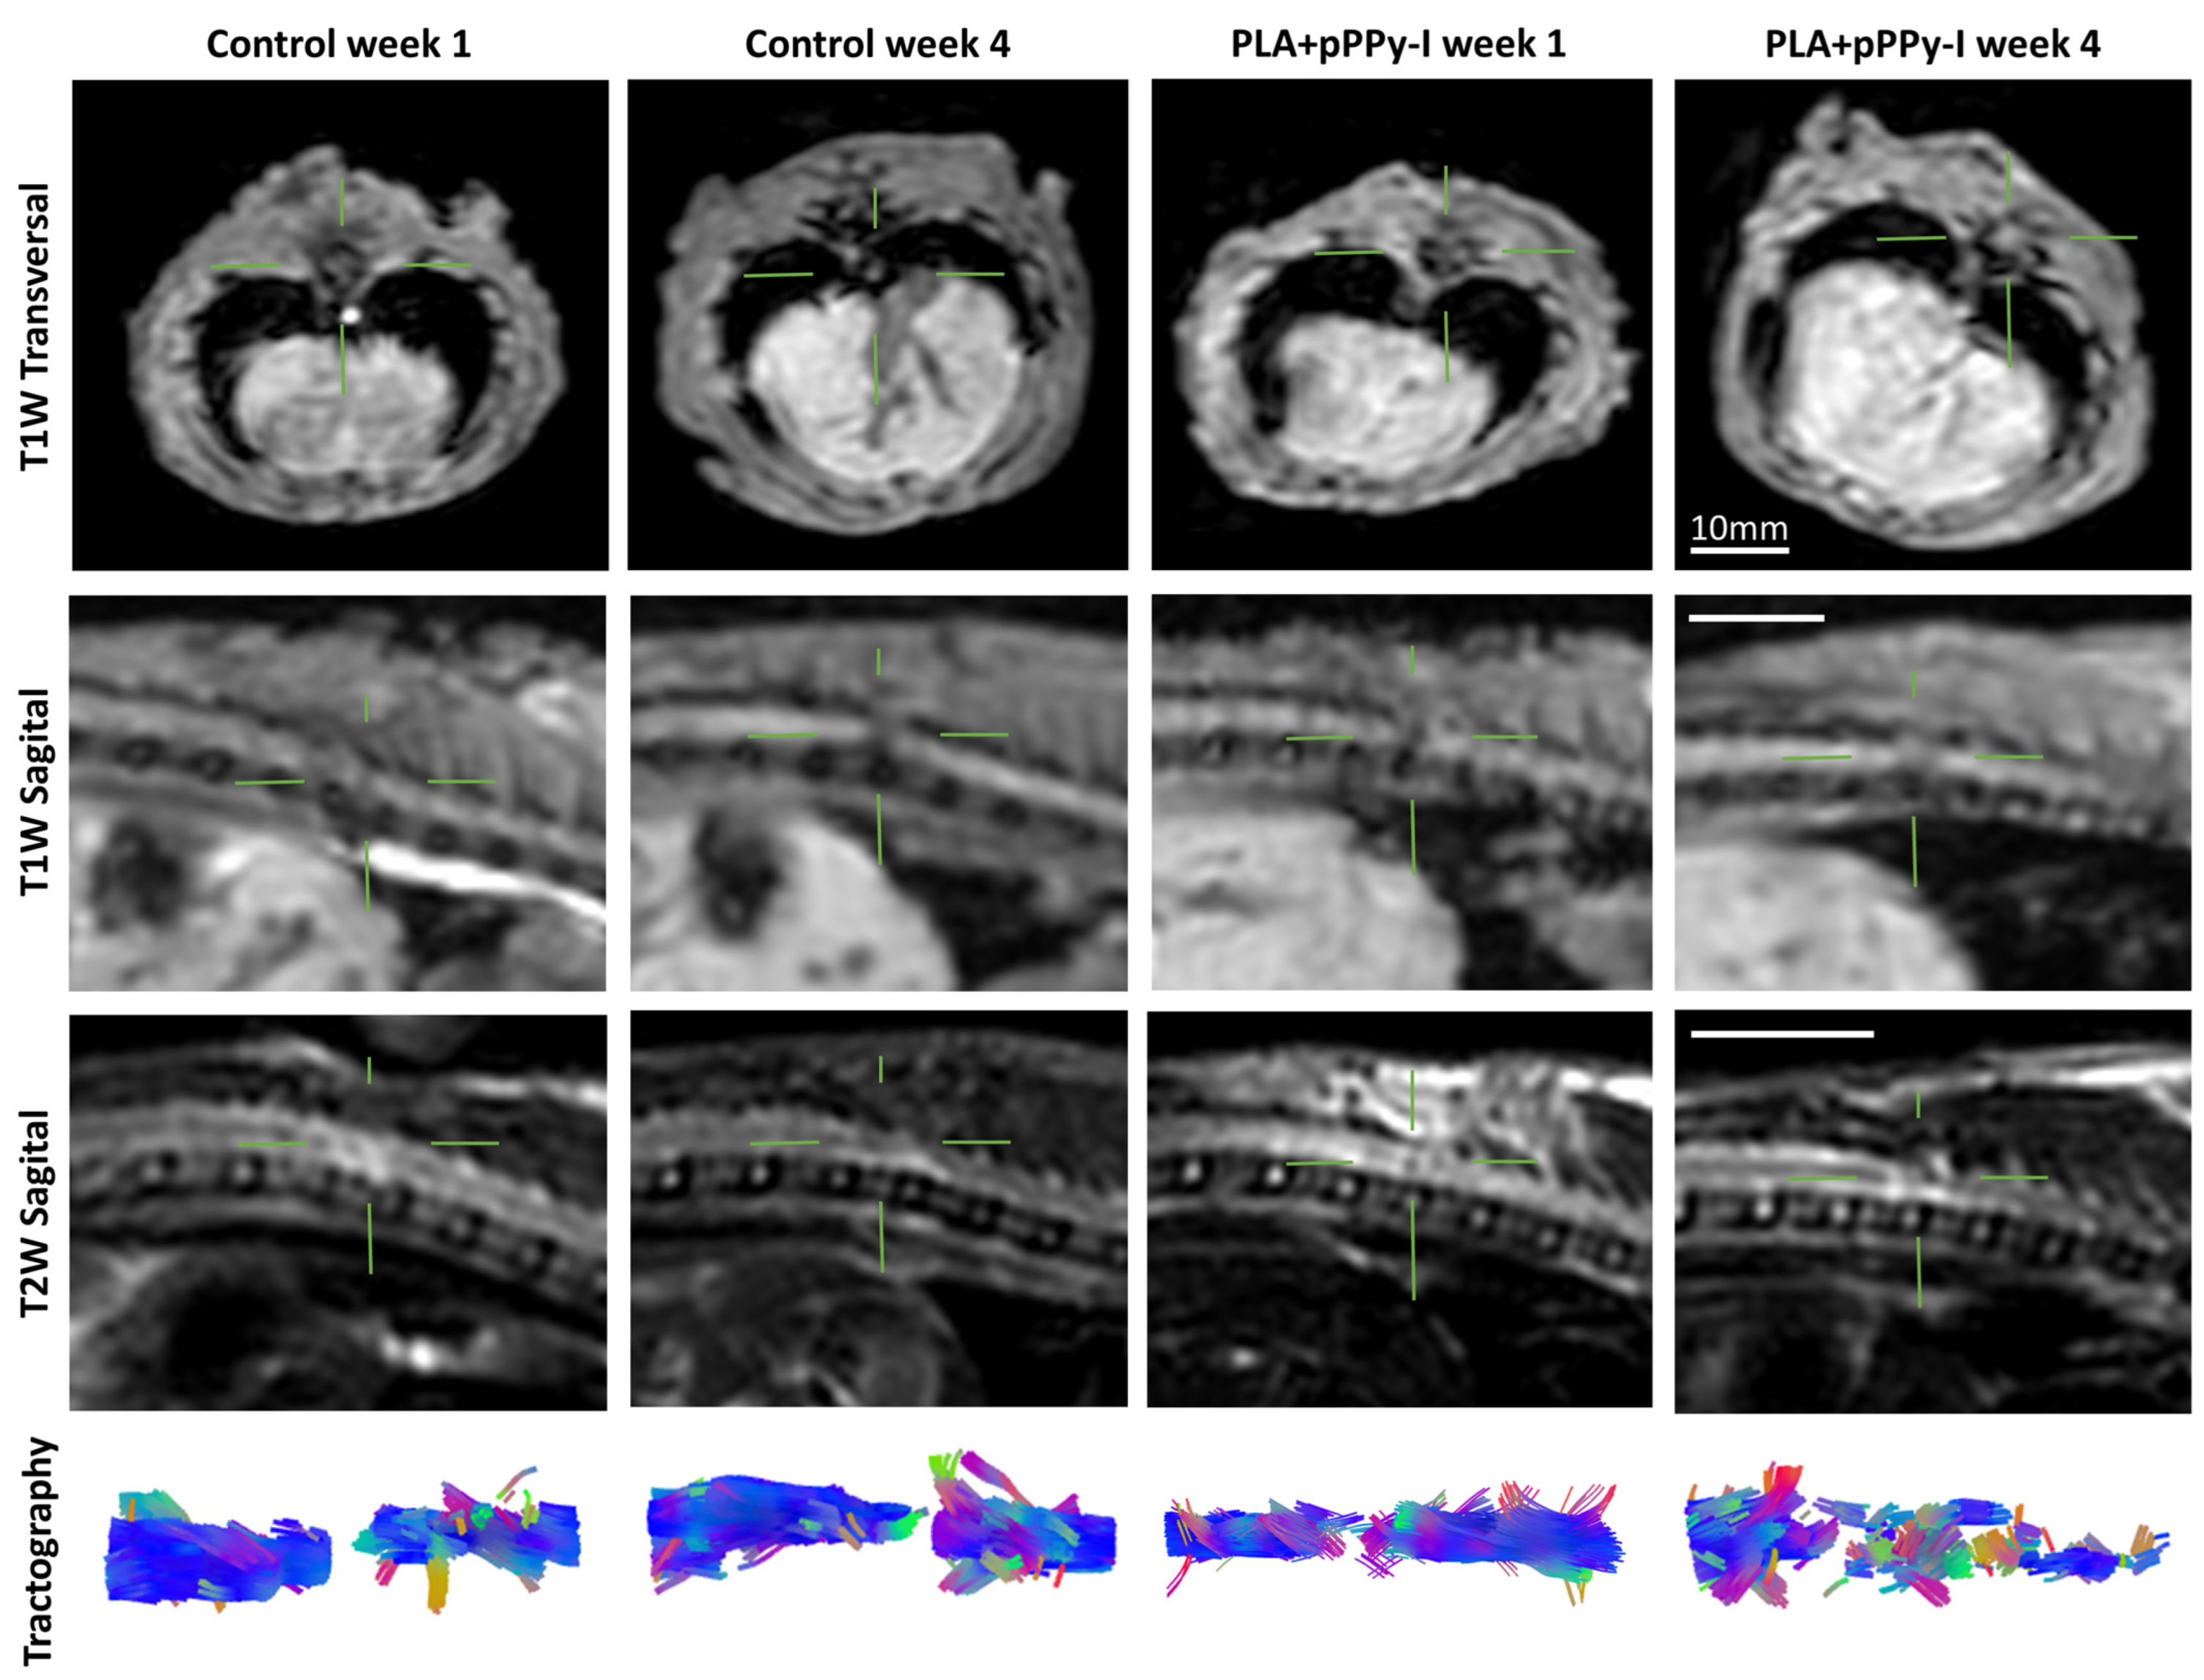

3.4. Recovery of Structural Damage by the Fibrillar Scaffolds

3.5. The Recovery of Anisotropy Baseline Values Suggests Neural Pathway Reorganization across the Scaffolds